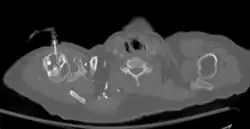

Axial CT with left humeral head EZ-IO (power driver device) infusion of contrast.

Intraosseous devices allow quick and safe access to the vascular system for fluid and drug administration. After proper education and training, medical professionals can obtain vascular access via the IO route of administration by using one of the multiple devices that have been approved by the FDA for 24-hour use.[7] There are several FDA approved IO devices, categorized by their mechanism of action:

1. Power Driver: EZ-IO By Arrow Teleflex.

• The EZ-IO device is a small device that works like a traditional drill and drill bit, consisting of a reusable, battery-powered driver and disposable, hollow IO needle.[15] A trigger allows for the IO needle to enter the bone marrow space at a preset length without any pressure being applied.[16] In the United States, the FDA has approved the use of the EZ-IO device in the proximal tibia and the head of the humerus.[16]